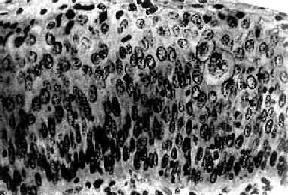

子宫颈原位癌(carcinoma in situ)癌细胞局限于上皮全层内、尚未穿破上皮基底膜侵入下方固有膜。子宫颈原位癌的异型细胞比不典型增生者更具显着的多形性。镜下,上皮层完全为癌细胞所取代,细胞大小、形状不一,呈圆形、卵圆形、梭形,偶见巨核、多核,排列紊乱,层次不清,极向消失。核大浓染、大小及形状不一、染色质增粗,核分裂像常见,并有病理性核分裂像。胞浆相对减少,核浆比值增大(图13-3)。原位癌癌细胞可由表面沿基底膜伸入腺体内,致整个腺管或其一部分为癌细胞所取代,但腺管轮廓尚存,腺体基底膜完整,癌细胞未浸润到固有膜。这种变化称原位癌累及腺体。原位癌累及腺体并不一定发展为浸润癌。部分子宫颈原位癌可长期不发生浸润,个别病例甚至可自行消退。但由于原位癌特别是原位癌累及腺体具有发展为浸润癌的倾向,故一旦发现,应及时给予适当治疗。

图13-3 子宫颈原位癌

癌变限于上皮层内,细胞核肥大、深染,大小不一,形态不规则,核仁明显,核分裂像易见,且见巨细胞(右侧上方),这种细胞间变累及上皮全层,但基底膜完整,癌细胞未浸润到基底膜下间质